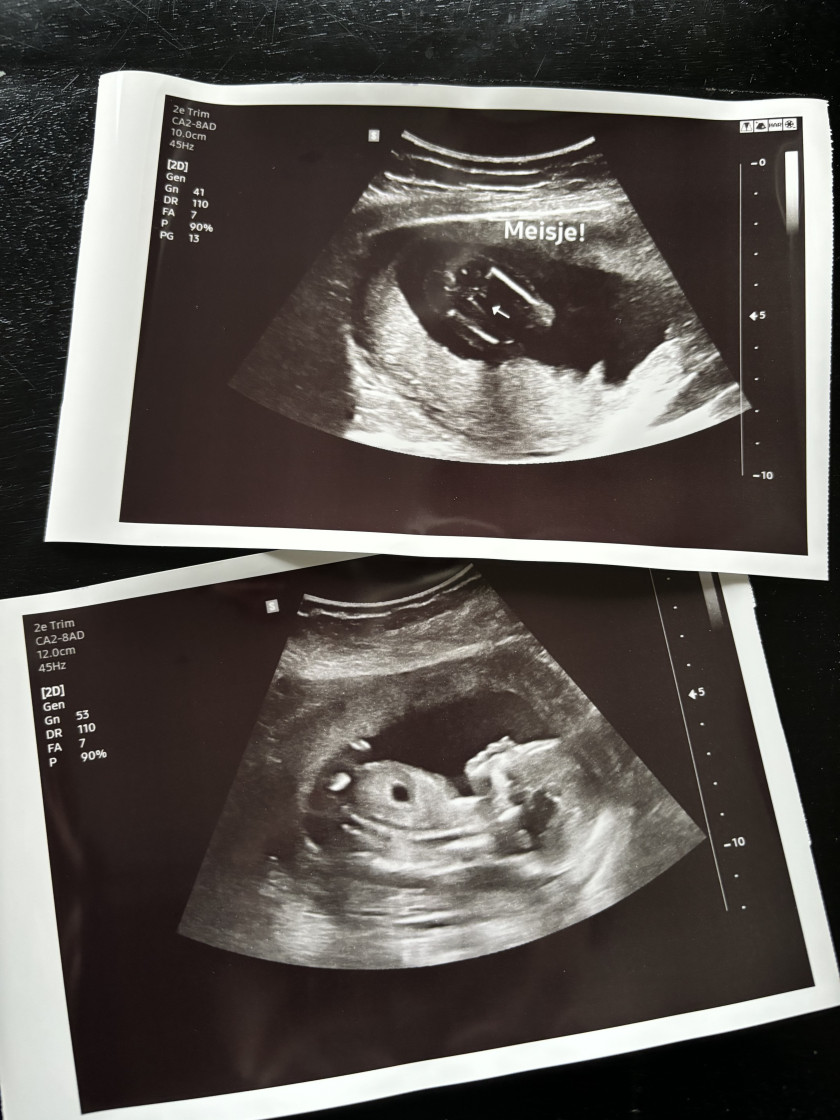

Ik ben Marion, ik ben 30 jaar, opgegroeid in Haren ( Groningen ) en samen wonend met mijn vriend, mijn dochter en mijn 2 lieve katten Bob en Marley.